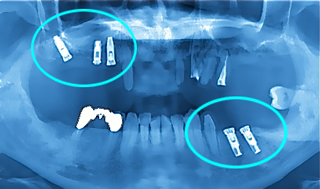

上アゴと下アゴにインプラント

コラム「上アゴと下アゴにインプラント」の画像